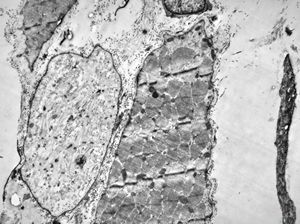

F,25y. | myopathy - atrophic and regenerating muscle cells